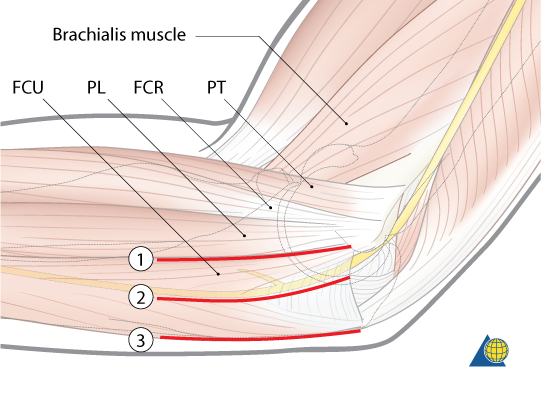

Hotchkiss Medial Over-the-top

Interval:

- Proximally: Intermuscular septum between triceps (radial n.) & brachialis (radial n, median n.)

- Distally: Through flexor pronator mass. FCU (ulnar n.) & FDS/Palmaris Longus (Median n.)

Approach: Unroof, identify and mobilize the ulnar n. Split flexor pronator mass, and elevate anteriorly. Care to be taken for MUCL

Dangers: Ulnar N. MUCL, Median N. Brachial A., MABCN (found on fascia anterior to septum)

FCU Split

Interval: None, between two heads of FCU (Ulnar N.)

Approach: Identify, unroof and protect median n. Split two heads of FCU and elevate anteriorly. Care to be taken not to injure MUCL

Dangers: MUCL, Ulnar N. Median N. Brachial A.

Modified Taylor and Scham

Interval: ECU (PIN), FCU (Ulnar N.)

Approach: Dissect down to subcutaneous boarder of ulan and lift everything anteriorly. Akin to the boyd but on the medial side. Gives access to base of coranoid/sublime tubercle

Dangers: Ulnar N., MUCL

*1 = Hotchkiss, 2= FCU Split, 3=Taylor Scham